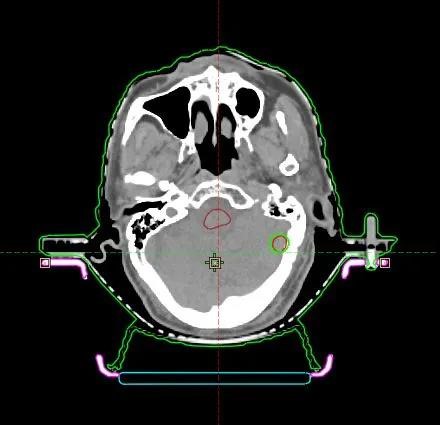

01 单发脑转移

肺癌单发脑转移,40Gy/10F,最大径4.77cm,

跌落到50%处方剂量仅需5mm,CI为1.03

2020年10月28日,首例HyperArc治疗开展,全程共10分钟,其中出束开始到治疗结束不到5分钟。因为治疗的高度自动化,技师无需进入治疗室重新对患者进行摆位或者手动移床,治疗时间远远低于常规非共面治疗。